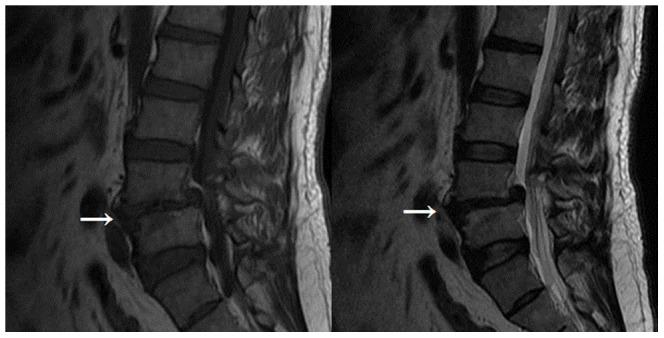

MRI assessment of lumbar intervertebral disc degeneration with lumbar degenerative disease using the Pfirrmann grading systems.

To evaluate by MRI intervertebral disc degeneration in patients with lumbar degenerative disease using the Pfirrmann grading system and to determine whether Modic changes correlated with the Pfirrmann grades and modified Pfirrmann grades of disc degeneration.

The clinical data of 108 surgical patients with lumbar degenerative disease were reviewed and their preoperative MR images were analyzed. Disc degeneration was evaluated using the Pfirrmann grading system. Patients were followed up and low back pain was evaluated using the visual analog scale (VAS) and the effect of back pain on the daily quality of life was assessed using Oswestry disability index (ODI).

Forty-four cases had normal anatomical appearance (Modic type 0) and their Pfirrmann grades were 3.77±0.480 and their modified Pfirrmann grades were of 5.81±1.006. Twenty-seven cases had Modic type I changes and their Pfirrmann grades were 4.79±0.557 and their modified Pfirrmann grades were 7.00±0.832. Thirty-six cases exhibited Modic type II changes and their Pfirrmann grades and modified Pfirrmann grades were 4.11±0.398 and 6.64±0.867, respectively. One case had Modic type III changes. Kruskal-Wallis test revealed significant difference in modified Pfirrmann grade among Modic type 0, I and II changes (P<0.01) but no significant difference between Modic type I and II changes (P>0.05). Binary regression analysis showed that Modic changes correlated most strongly with disc degeneration. Follow up studies indicated that the VAS and ODI scores were markedly improved postoperatively. However, no difference was noted in VAS and ODI scores among patients with different Modic types.

Modic changes correlate with the Pfirrmann and modified Pfirrmann grades of disc degeneration in lumbar degenerative disease. There is no significant correlation between Modic types and surgical outcomes.